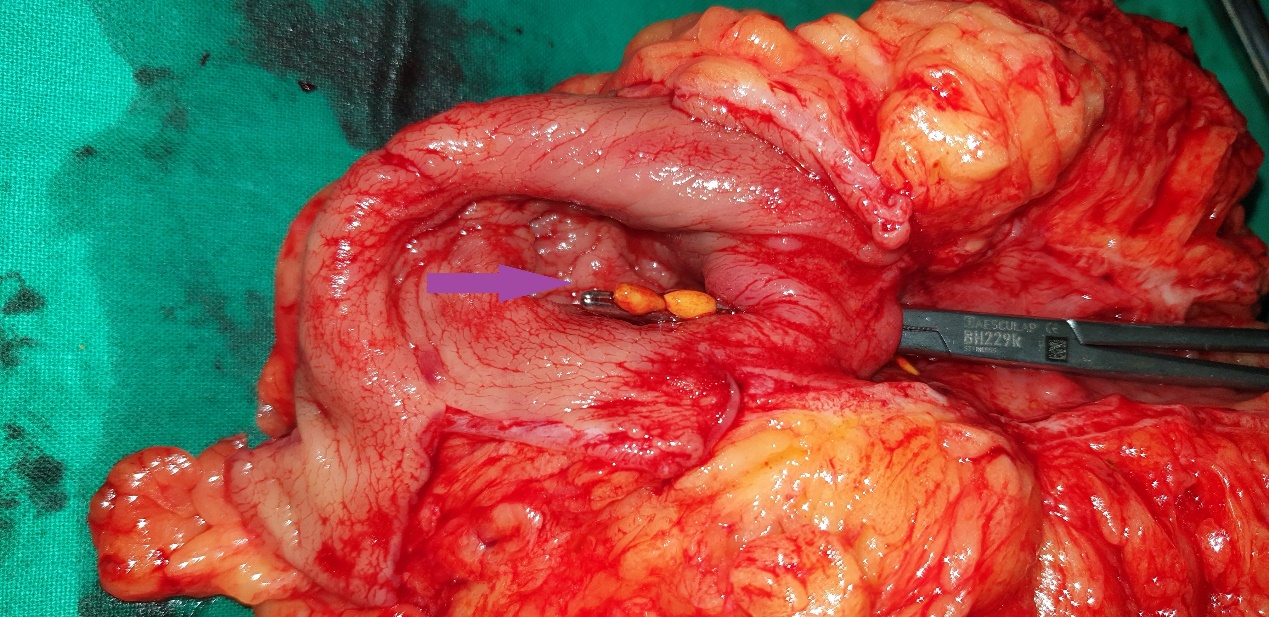

Anatomical forceps within the fistula orifice in the duodenum (Courtesy Dr. V. Penopoulos)